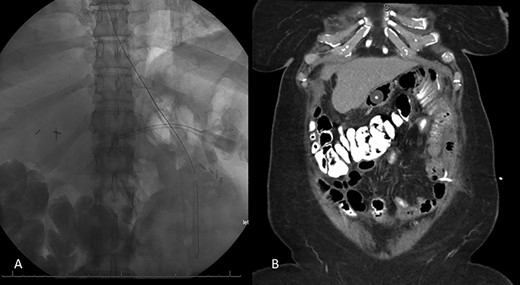

The patient is a 46-year-old female with a pre-operative body-mass index (BMI) of 48 kg/m2 who underwent an uneventful laparoscopic RYGB with a 50-cm biliopancreatic limb and 100-cm alimentary limb and an antecolic, antegastric-stapled gastrojejunostomy using a 21–3.5-mm circular stapler in addition to the repair of a small sliding hiatal hernia. A thick omentum was divided in the midline, starting at the level of the mid-portion of the transverse colon moving distally through the edge of the omentum (Fig. 1). The procedure was uneventful, and the patient was discharged home on postoperative day 1. She had a scheduled follow-up visit at 2 weeks and was progressing as expected. Three weeks postoperatively, she presented to the emergency room complaining of two-day history of severe, diffuse abdominal pain. Initial vital signs were normal and laboratory values were WBC of 6.7 109/L, creatinine 0.76 mg/dl and lactate of 1.2 mmol/L. CT scan was obtained (Fig. 2A and B) that demonstrated 17.7 cm partially encapsulated mixed attenuating area on the right side of her abdomen, suggestive of omental infarction with necrosis. There was no evidence of leak from GJ or JJ anastomoses on CT with oral contrast, which was subsequently confirmed on upper GI with small bowel through. She was admitted for observation. Over the course of the next day, she reported worsening abdominal pain and developed tachycardia to 117 and BP of 89/68 mmHg. Repeat WBC count was 12.7 109/L, creatinine 1.29 mg/dl and lactate of 5.0 mmol/L.

A and B: Abdominal and pelvic CT scan obtained at POD # 21 readmission for abdominal pain showing a 17.7-cm mixed attenuating lesion extending anterior to the transverse colon into the upper-pelvis-associated stranding and fluid level suggestive of omental infarction and liquefied necrosis.